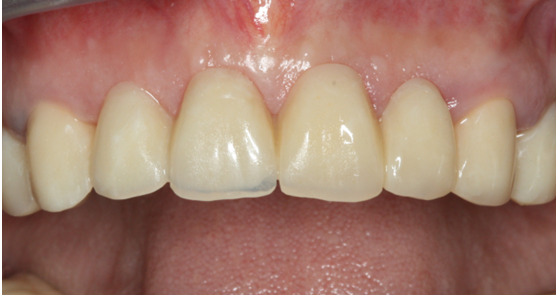

Στην ασθενή οι τομείς στην άνω γνάθο είχαν χαθεί λόγω τερηδόνας. Στην περιοχή τοποθετήθηκαν δύο εμφυτεύματα και έγινε μία γέφυρα τεσσάρων τεμαχίων (δοντιών) επί αυτών.

Η κλινική εικόνα μετά την τελική αποκατάσταση (γέφυρα) κρίνεται απόλυτα επιτυχής.

Τελική Φωτογραφία